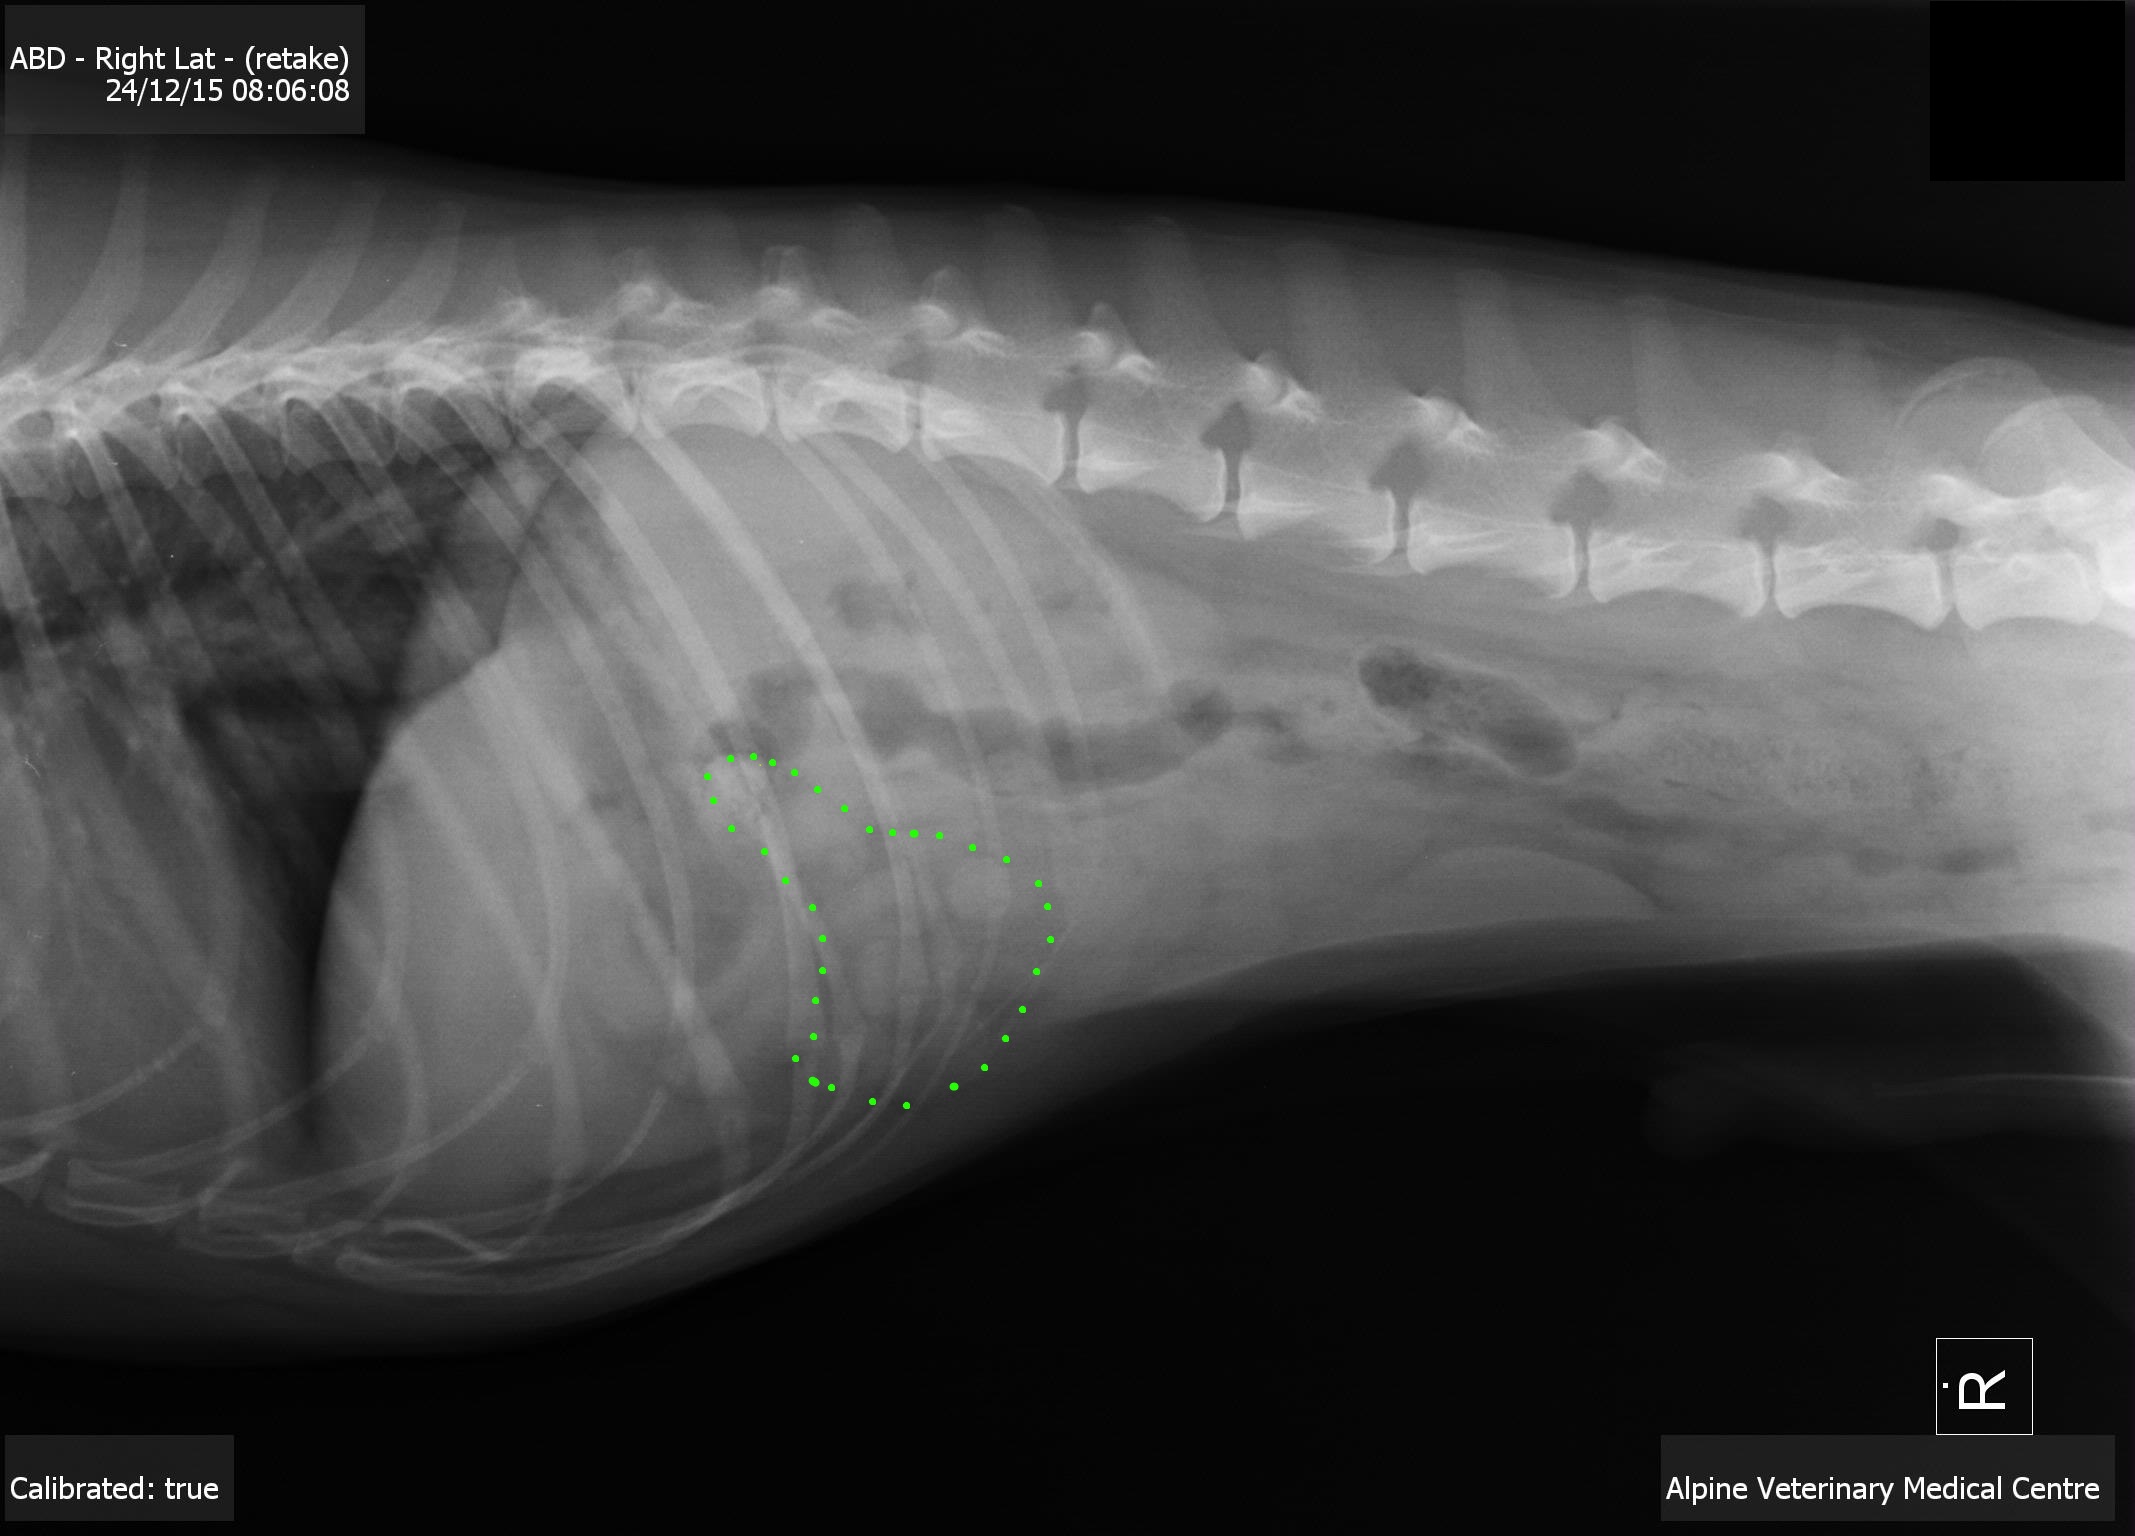

When I see young dogs that are full of energy but can't keep anything down, I start worrying about possible obstructions in the stomach or bowel. Dogs that are more obviously "sick" and showing signs such as diarrhea, dehydration and fever are dogs where I worry about infectious or metabolic disease, like pancreatitis or kidney failure. Jake did not seem like a sick dog, so I recommended taking x-rays to see if we could find an obstruction.

This x-ray is looking at Jake from the side - his head is on the left, and his tail is to the right. The area outlined in green shows bunched, abnormal looking intestines.

Jake's x-rays fell in the frustrating grey area of "not awful and not normal." I was worried that he had some bunching of his intestines behind his stomach, and that his spleen was displaced relative to where it would be normally found. Jake's owner and I discussed that while I was suspicious he had a bowel obstruction, I couldn't prove it. While there was a chance that we could do an exploratory surgery and turn up nothing, there were severe consequences to missing a bowel obstruction, including lack of food and water absorption, death of bowel tissue, and possible sepsis or death.